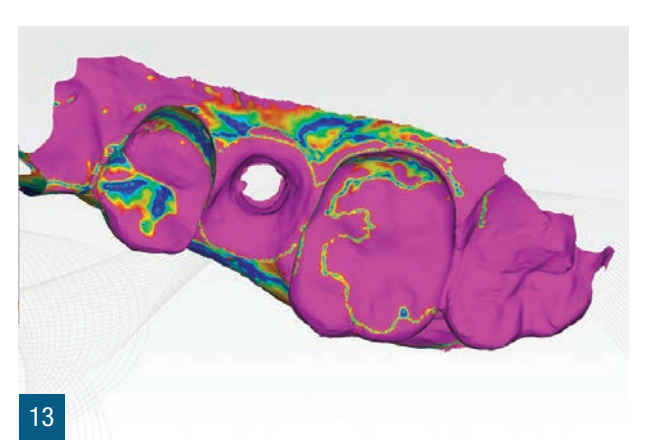

Пацієнтка 36 років звернулася до нас з частковим переломом коронки другого премоляра праворуч (1.5). Після перевірки неможливості консервативного відновлення було заплановано імплантно-протезне лікування з негайною екстракцією для заміни ураженого елемента (Рис. 1,2). Пацієнтка, не курець, була класифікована як ASA 1. Було виконано локалізовану CBCT в ураженій області для перевірки наявності та морфології вестибулярної кісткової стінки навколо елемента, що підлягає екстракції, в альвеолярному відростку. Перед екстракцією 1.5 була виконана цифрова внутрішньоротова відбитка (iTero Flex, Align Technology) зуба та прилеглих ділянок (Рис. 3). Після плескальної анестезії була виконана екстракція, обмежуючи травму пародонтальних тканин, розділяючи корені та використовуючи міні-важелі та синдесмотоми для збереження вестибулярної кісткової пластини. Оцінюючи цілісність альвеоли та сприятливі анатомічні умови, переходять до встановлення імплантату розмірів, що забезпечують адекватну первинну стабільність (4.1 x 11,5 TSVH ZimmerBiomet). Імплантат розміщується в близькій до піднебіння позиції відповідно до вказівок літератури (Рис. 6,7), заповнюючи проміжок між імплантатом та вестибулярною кістковою кортикою за допомогою гетерологічної кісткової пересадки (Copioss Zimmer-Biomet). Монтажний пристрій формують так, ніби це абатмент, і після його закручування на імплантаті проводять сканування. З цифрового внутрішньоротового сканування виконується CAD проектування гвинта загоєння (Рис. 4). У проекті буде використано як передекстраційне сканування, так і сканування з монтажним пристроєм, перетвореним в абатмент, щоб максимально точно відтворити гвинт загоєння. Морфологія гвинта загоєння відтворить існуючі тканинні умови на момент хірургії та дозволить уникнути естетичних дефектів у рожевій естетиці. Завершивши цифрове проектування, виконується 3D-друк з смоли (Lab2 Formlab) кастомізованого гвинта загоєння. Після завершення друку, отриманий гвинт загоєння з смоли Nextdent цементується з авто- та фото-твердим смолистим цементом (Relix Unicem, 3M) до абатмента, отриманого з монтажного пристрою, а потім закручується на імплантат (Рис. 5,6). Було проведено рентгенологічні контролі через три місяці та через рік (Рис. 7,8). Через 3 місяці була виготовлена остаточна коронка через цифровий потік з тим самим сканером та спеціальними сканбоді (Gentek, Zfx), які дозволяють ідентифікувати точне просторове положення імплантату. Через тиждень була передана остаточна монолітна коронка з фарбованої цирконії, закручена на ti-base (Рис. 9,10). Через рік було виконано ще одне сканування для оцінки з часом можливих об'ємних змін періімплантних тканин. Сканування, виконані на етапі передекстракції та через рік, були оброблені за допомогою спеціалізованого програмного забезпечення (meshlab) для оцінки розмірних змін (Рис.11-13).

У зв'язку з клінічними цілями, описаними Тарновим та співавторами, з цього клінічного випадку видно, як одночасна стабілізація кісткового сайту та заповнення існуючого зазору гетерологічним матеріалом дозволяє зберегти горизонтальні та вертикальні об'єми постекстракційного сайту. Швидкість і легкість виконання кастомізованого загоювального гвинта за цією методикою дозволяє покращити герметичність трансмукозного шляху та зберегти морфологічні та об'ємні характеристики до екстракції. Якщо використовувати неанатомічні загоювальні гвинти більшого діаметра, ми, безумовно, отримаємо кращу герметичність у порівнянні з класичними стандартними загоювальними гвинтами, але вони не дозволять точно відтворити межі постекстракційного сайту, як кастомізований загоювальний гвинт, отриманий за аналоговою та/або цифровою методикою. Цифровізація дозволяє суттєво скоротити час виконання та забезпечити більшу персоналізацію отриманого виробу. Точне відтворення існуючої ситуації, ймовірно, може гарантувати імпланту меншу кількість обслуговуючих втручань, таких як закручування та відкручування, на етапах проби. Цей клінічний випадок пропонує, як стабілізація періімплантних тканин може забезпечити оптимальне загоєння та зрілість тканин, спрощуючи фінальні етапи протезування. Це може дозволити уникнути подальших втручань для управління періімплантними тканинами, таких як повторні хірургії, пересадки та використання тимчасових конструкцій. Етап CAD дозволяє точно відтворити профільEmergence, копіюючи форму шийки зуба. Крім того, слід врахувати, що аналогове виготовлення загоювального гвинта вимагає простоїв, які можна використовувати для інших цілей, і тому в управлінні під час операції прискорюється робочий процес і досягнення кінцевого результату. Використання цифрових сканувань до та після хірургії дозволило порівняти об'єми періімплантних тканин, накладаючи сканування до та після хірургії через три місяці та через рік, щоб виявити об'ємні зміни. Це корисний інструмент для можливих клінічних оцінок, а також для комунікації з пацієнтом.